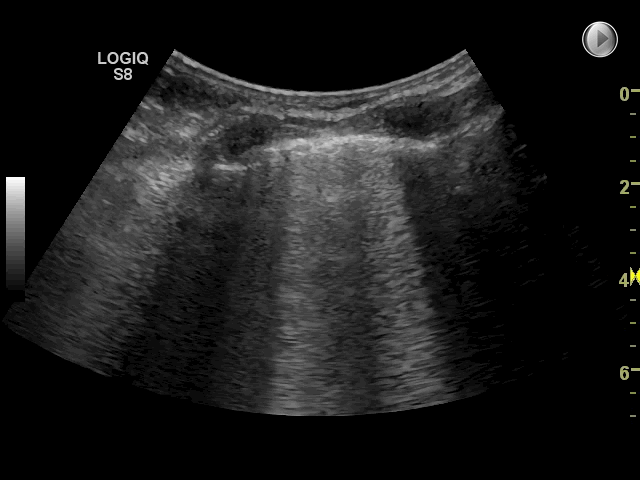

The following ultrasonographic signs are suggestive of pulmonary edema:

• Multiple B-lines (>2) between two costae in more than one view bilaterally

The following ultrasonographic signs rule out pulmonary edema:

• Absence of multiple B-lines between two costae in more than one view bilaterally